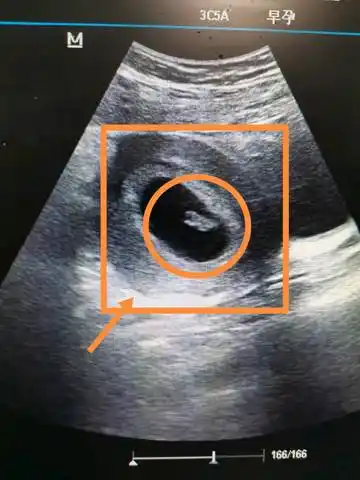

6 5查的胎心胎芽,孕囊偏大两周,孩子偏大一周,愿我的小宝贝健康平安

热乎乎的胎心胎芽来了,医生说长的挺好的,安安心心的养胎啦!

还愿,46天见胎心胎芽